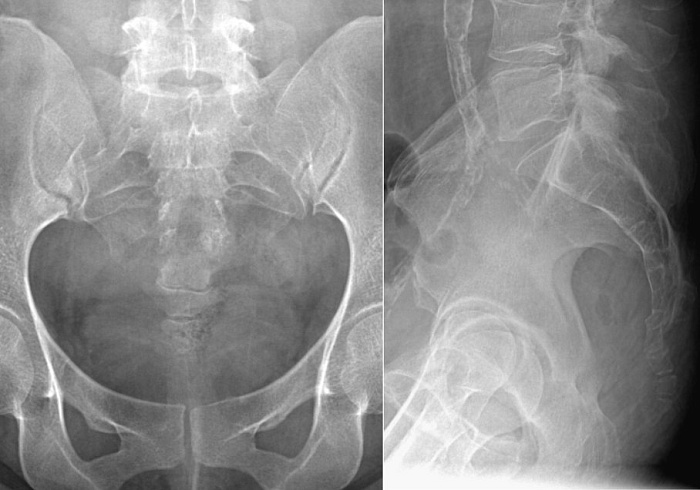

Рентгенография копчика – важный метод прицельного исследования, который позволяет оценить состояние копчика.

Диагностическая услуга выполняется в двух проекциях.